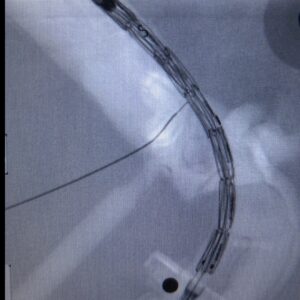

In questo primo caso, la procedura ha previsto prima la costruzione su banco della PMEG partendo da una endoprotesi standard tubulare di calibro 26mm. Il progetto della PMEG è stato eseguito utilizzando un modello TAC guidato. Una volta modificata l’endoprotesi è stata impiantata nel modello aptico mediante tecnica endovascolare utilizzando la sala operatoria di Niguarda dove è stato possibile procedere al rilascio ed alla cannulazione dei vasi celiaco, mesenterici e renali. La simulazione della PMEG è stata completata in circa 3.5 ore dall’inizio della progettazione del modello PMEG fino alla cannulazione dei vasi. La tempistica è stata monitorata anche per rendere il modello riproducibile in emergenza e creare pertanto un processo decisionale cronologicamente efficace sia in elezione che in urgenza.